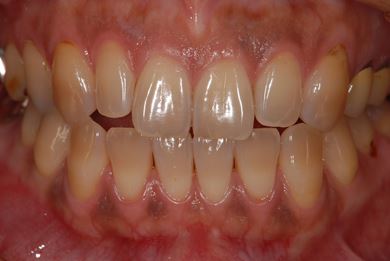

治療後

• 治療後